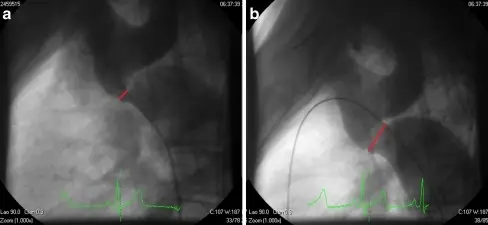

A patent ductus arteriosus (PDA) results from failure of the ductus arteriosus close.

Patent ductus arteriosus (PDA) results in a left-to-right shunt between the pulmonary artery and the aorta.

The ductus arteriosus generally diverts blood away from the lungs and toward the aorta during development.

Patent ductus arteriosus (PDA) is typically asymptomatic at birth with a holosystolic ‘machine-like’ murmur.

Patent ductus arteriosus (PDA) may result in lower extremity cyanosis and Eisenmenger syndrome.

Treatment of patent ductus arteriosus (PDA) involves indomethacin, which decreases prostaglandin E1 (PGE1), resulting in PDA closure.

Note that PGE1 maintains patency of the ductus arteriosus.

Prostaglandin E1 (PGE1) can be given to keep a patent ductus arteriosus (PDA) open until a permanent surgical repair is made.

A patent ductus arteriosus (PDA), infantile form is connected.

Coarctation is located distal (after) to the aortic arch and proximally (before) to the patent ductus arteriosus (PDA).